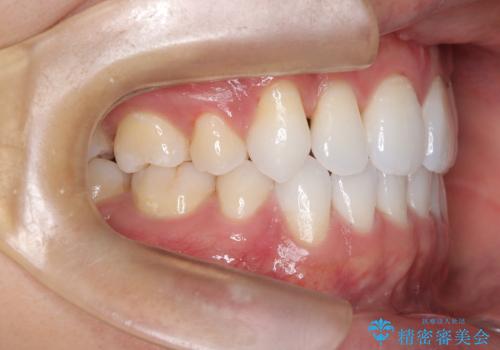

治療完了後、重なり合っていた歯はきれいに整い、懸念されていた前歯の突出も一切起こることなく、理想的な噛み合わせを実現しました。装置が目立ちにくかったため、治療期間中も周囲の目を気にすることなく、前向きに治療に取り組んでいただくことができました。